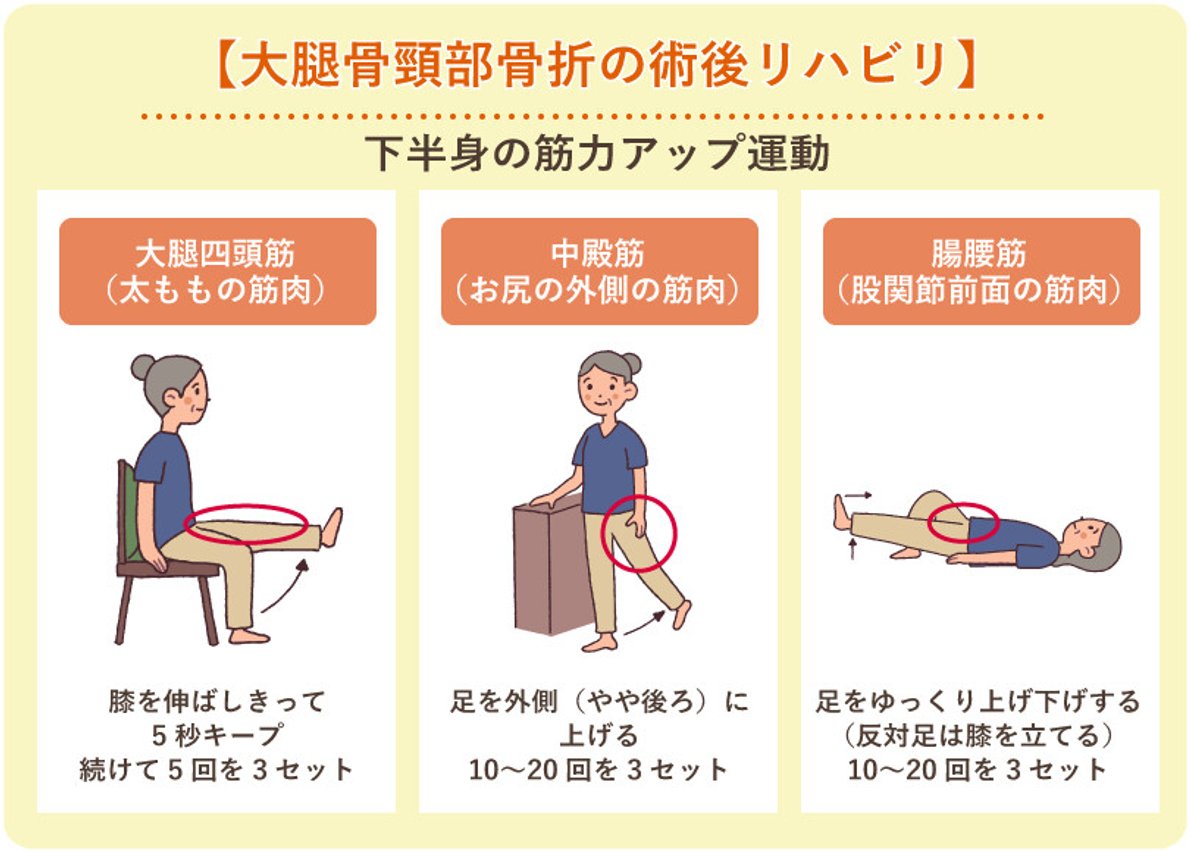

5. リハビリや運動に対するモチベーションを与える

リハビリ計画を遵守することが重要です。多くの人にとって、これは 1 日に 2 ~ 3 回 30 分間歩くことを意味します。医師は、1 日に 2 ~ 3 回、さらに 20 ~ 30 分間の運動を推奨することもあります。

歩いたり運動したりすると痛みを感じることがあります。これは正常です。患者がリハビリ計画を中止したいという意思を表明した場合は、彼らが感じていることはよくあること、リハビリが回復を早めるのに役立つことを思い出させてください。

自分の努力、結果、進捗状況をグラフ化できるようにすると、モチベーションを維持できる可能性があります。子どもたちと一緒に運動したり歩いたりすることも、子どもたちが順調に進むのに役立つかもしれません。